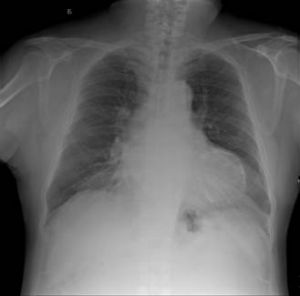

3.X 線和CT 檢查 普通胸片可顯示主動脈結鈣化,高曝光技術或斷層攝片可提高檢出率。如在主動脈和(或)二尖瓣環處出現斑片狀、線狀或帶狀鈣化陰影,有助於診斷。此外可出現主動脈瓣和二尖瓣狹窄與關閉不全相應的X 線徵象。另外,Woodring 等報導對於某些超聲未能檢出的早期老年鈣化性瓣膜病。CT 可提高檢出率,且認為比超聲有更高靈敏性和特異性,但尚不是常規的檢測方法。